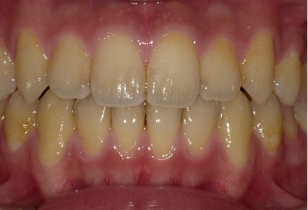

しかし当院の歯並びもよく観察すると、少しは指数が増加、つまり多少は歯並びが悪くなっていることが分かります。実はこれは自然な歯並びの変化と同じものである事がわかりました。つまり歯並びは下の写真が示すように矯正をしてない人でも、変化するのです。その自然な変化をリトル教授のお仲間のシンクレア先生が報告しており、そのデータを追加したのが下の図です(グラフのグレー)。これをみると元々綺麗な歯並びだったものも7年経過するとリトルの指数が35%も増加していることが分かります。

自然な歯の移動